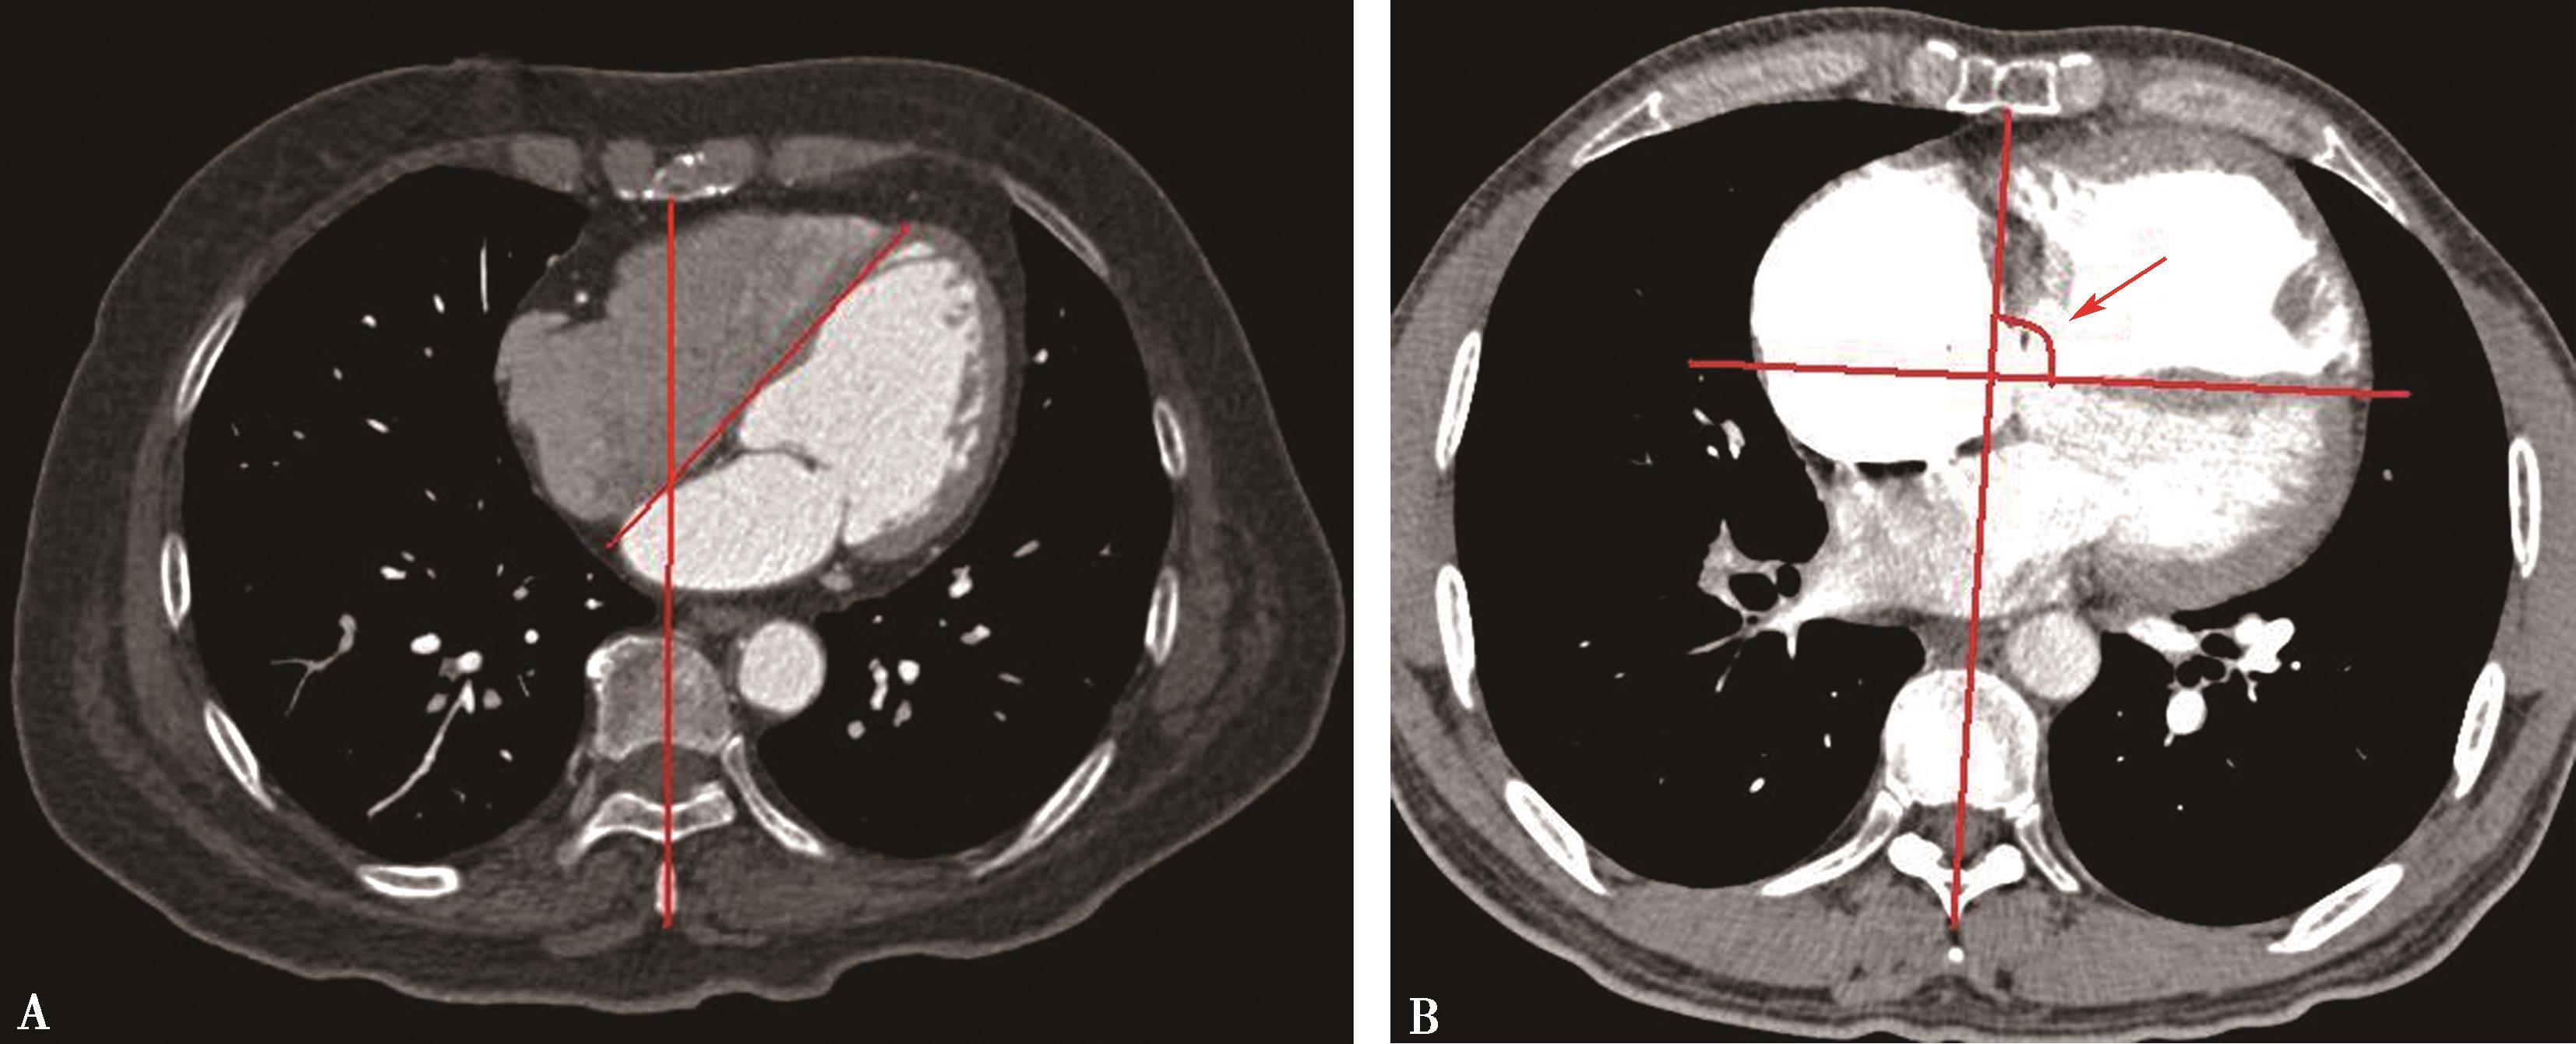

1.右心室增大

横断像心室最大层面测量左右心室最大横径(图8-3-10),正常心脏右心室横径:左心室横径<1,(a∶b<1),室间隔居中(红色↑)。右心室增大,右心室横径:左心室横径>1,(a∶b>1),室间隔凸向左心室(红色↑)。

2.右心室增大心脏顺钟向转位

横断像心室间隔与纵轴夹角可以反映右心室增大;由于右心室增大,心脏顺钟向转位,室间隔与纵轴夹角增大(图8-3-11)。

图8-3-10 横断图像

A.正常心脏,a∶b<1; B.右心室增大,a∶b>1

图8-3-11 横断图像

A.正常心脏;B.右心室增大,顺钟向转位,室间隔与纵轴夹角增大(↑)